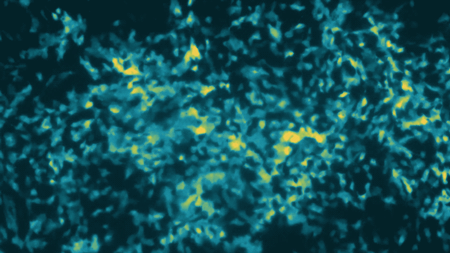

登录/注册后可看大图

不断增殖的癌细胞